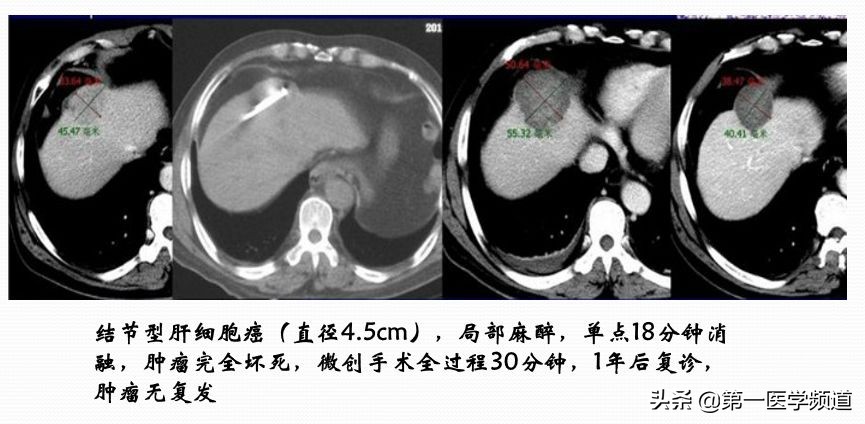

这是一个典型的微波治疗肝癌患者的案例。肝脏内比较大的肿块,接近5cm左右,我们通过8个位点做消融治疗,取得比较好的效果,术后肿瘤完全坏死。

这是一个典型的病例,胃癌术后肝门淋巴结转移导致的梗阻,主要是左肝管和总胆管的中段阻塞。我们放了两枚支架,左肝管和胆总管分别放一个支架。